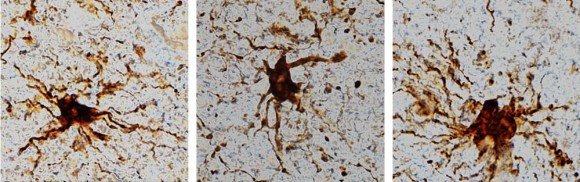

人間の脳の死後動き出すゾンビ遺伝子 credit:Dr. Jeffrey Loeb/UIC

いずれも「グリア細胞」という炎症細胞と関係しており、成長して腕のような枝まで伸ばし始めたという。これらは通常、脳が損傷したり、脳卒中を起こしたりすると、急に活動し始める細胞だ。

ゾンビ遺伝子は死んでから活性化し、12時間後にそのピークを迎える。

問題だったのは、脳組織が摘出されてからかえって活性化した遺伝子があったことだ。研究グループはそれを「ゾンビ遺伝子」と呼んでいる。